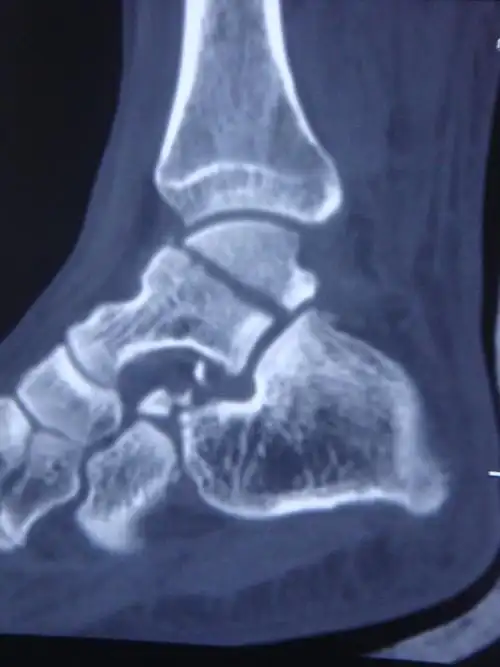

足部骨折-1 距骨骨折图片 - 好大夫在线

开放距骨骨折脱位合并内踝骨折病例分享

两例距骨体骨折病例—踝关节截骨入路螺钉内固定治疗距骨体骨折

距骨骨折的治疗!(附图片)